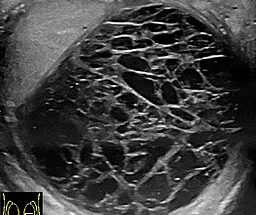

Wyborczyny wokół rany operacyjnej

Zasinienie wokół rany - to wybroczyny Wybroczyny to małe krwotoki podskórne, które mogą wystąpić w okolicy blizny po operacji. Są to małe, czerwone, niebieskie lub fioletowe plamki, które wyglądają jak drobne siniaki.